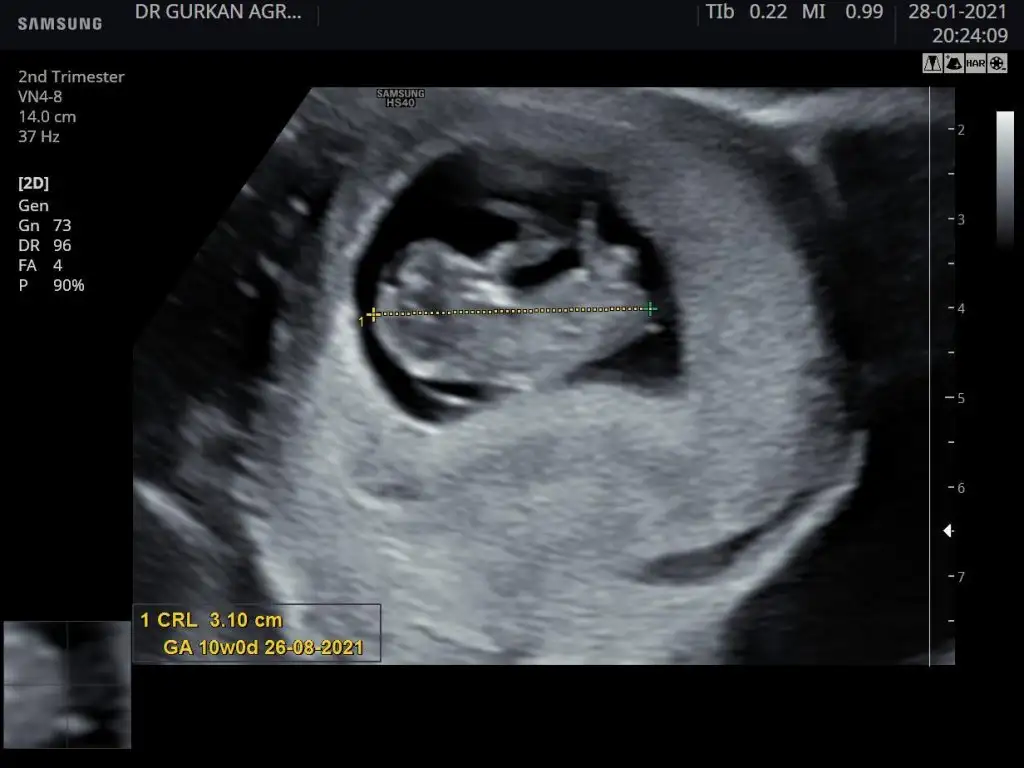

Erkek gibiEn baştaki 6+6 günlük olan diğer son 2 fotoğrafta 10 haftalık benimde tahmin edebilir misiniz

Kiz gibiÖnemli olan sağlıklı olsunAma cinsiyet ne olabilir